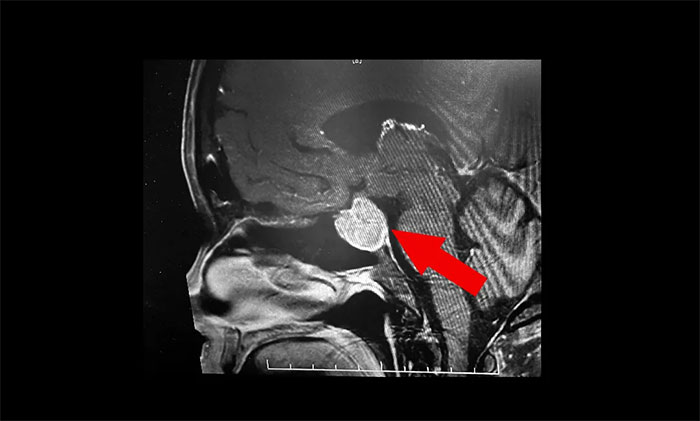

鞍区MRI平扫+增强显示:蝶鞍显著扩大,鞍区见不规则状肿块,大小超3公分。病变向鞍上生长,突入鞍上池,推移视交叉;向鞍旁生长,侵及左侧海绵窦,海绵窦内颈内动脉包裹,继续向侧旁生长,毗邻左侧颞叶受压内移向后生长。

▲ 影像显示垂体占位,侵犯海绵窦

李士其教授、潘仁龙主任、吴治群博士组成的专家组会诊后,考虑为侵袭性巨大垂体腺瘤。从影像学资料上看,瘤体已经十分巨大,占据鞍区,并向蝶窦和鞍上发展,侵袭左侧海绵窦,视神经、视交叉受压,应立即施行手术切除,解除压迫,若任其发展,将面临失明的风险。